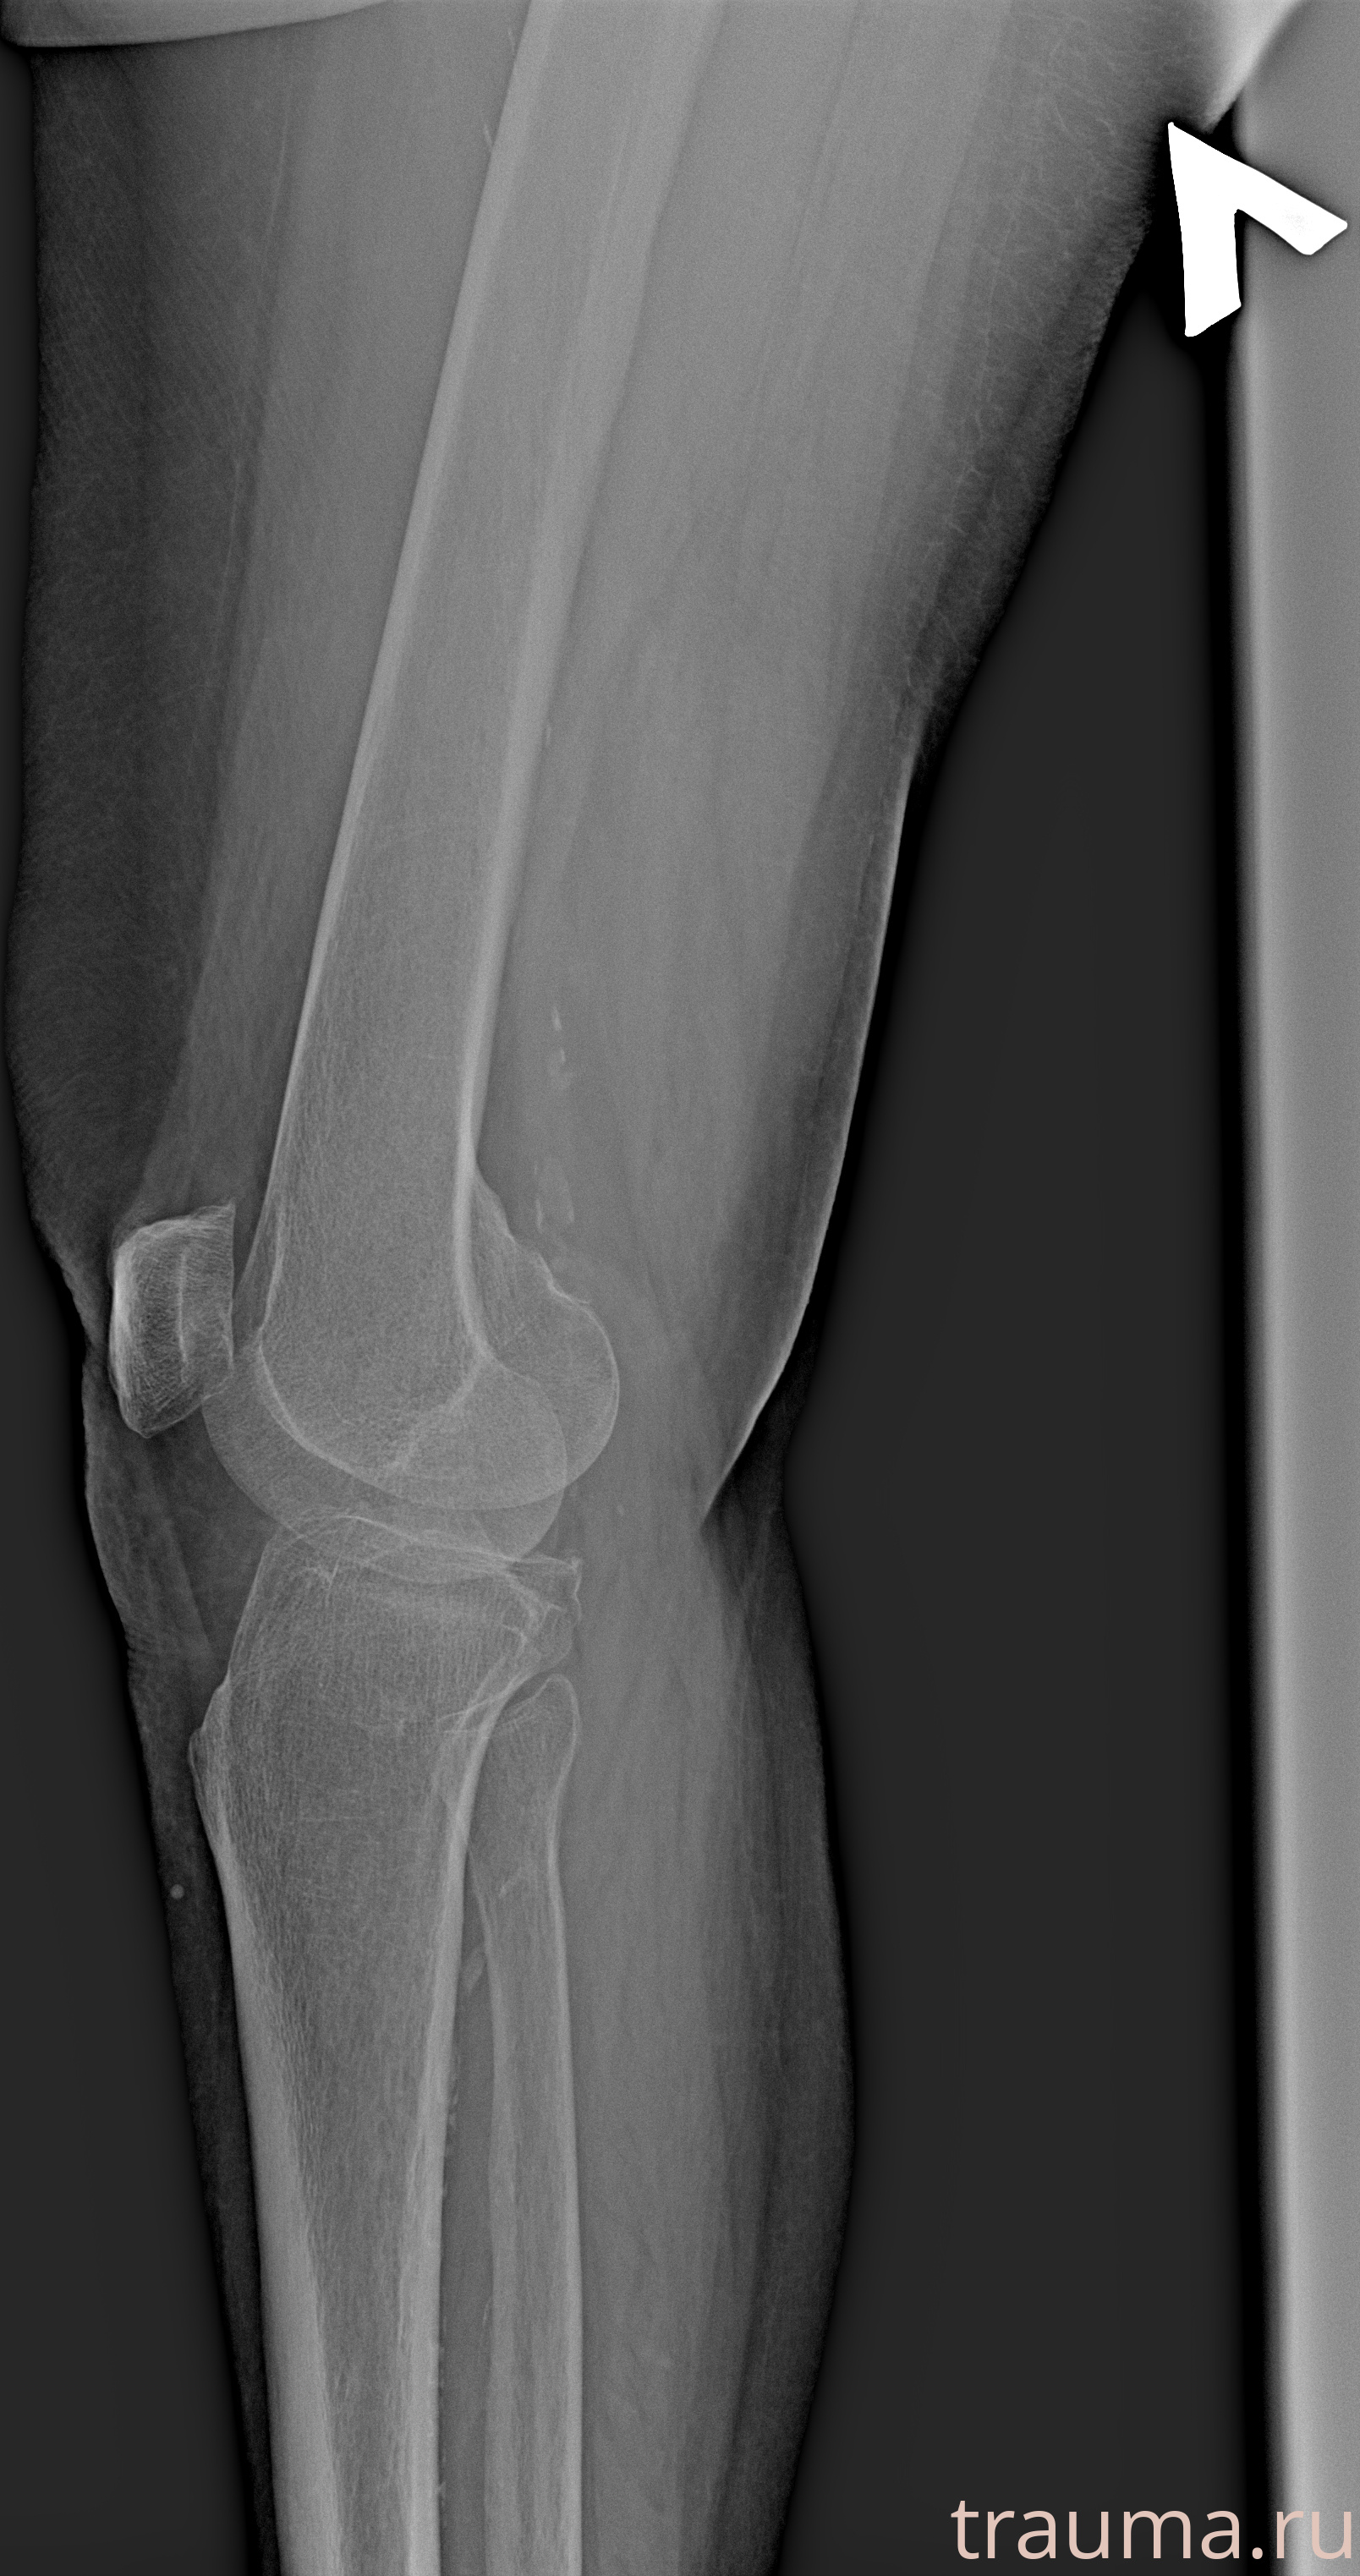

Рентгенограммы

Рентген на дому: по вашему адресу приезжает врач-рентгенолог, травматолог-ортопед с мобильным рентгеновским аппаратом, проводит диагностику травмы или заболевания, делает необходимые рентгенограммы, дает рекомендации по дальнейшему лечению. Получить качественные снимки в домашних условиях возможно благодаря уникальной методике, разработанной МосРентген Центром для института  Склифосовского